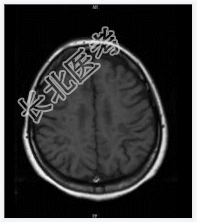

- [材料题] 患者女,28岁,反复左下肢无力4年余,痛觉减退2月余。查体:神清,左局部触觉减弱,左下肢肌力Ⅳ级,双巴氏征(+)。2001年MR示:脑脱鞘改变。行头颅MR平扫。

- 简答题1、诊断及依据是什么?

- 简答题2、鉴别诊断有哪些?